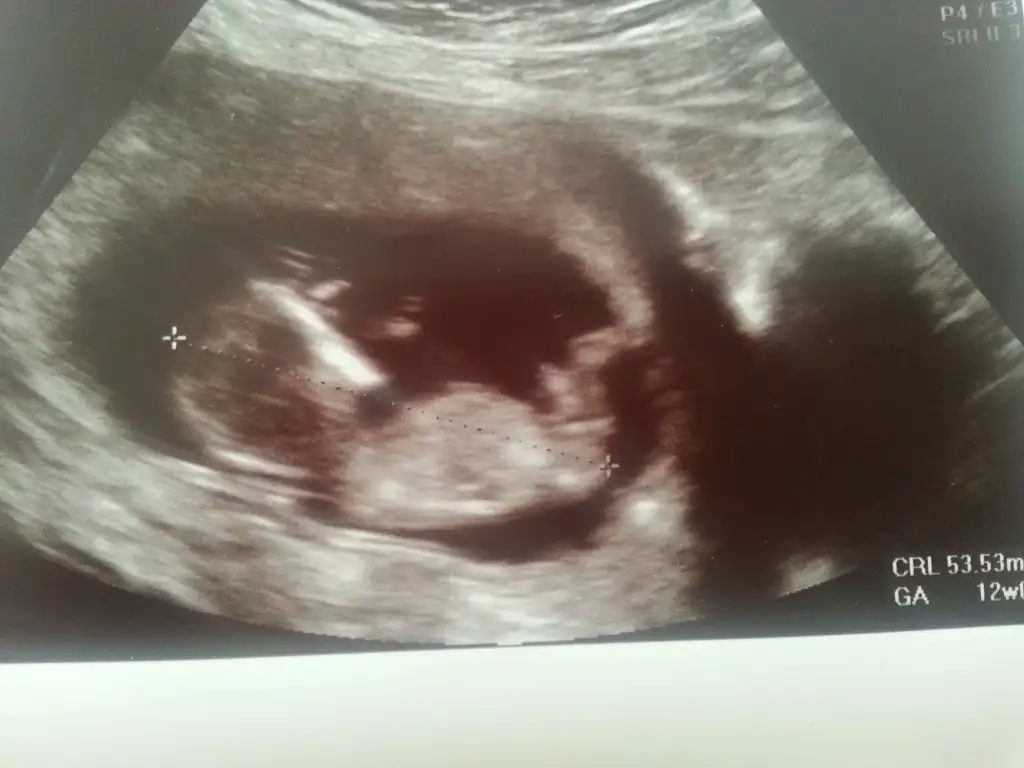

dr soylemeden siz gorun genital nub teorisi ( bebegin cinsiyeti)

Canim doktor kiza veya erkege benziyor demedimi hic neredeyse 4 bucuk aylik 12. Haftalik nubundan belli olmadimi peki? Canim dopplere giriliyor ya 20. Haftada kesin gorunur damarlarini bile incelemislerdi oglumun hic bi testi yaptirmadim ama dopplere girdim hemde cok guzel bir ani kaldi elimde kesinlikle girmeni tavsiye ederim :))

bir de kızlar, akşam oğlumun ultrason fotolarını buldum, yahu bizim oğlanın nubu bildiğiniz kızmışşş:KK57: bunda da nubu direk erkek bakalım ne çıkacak bahtımıza:KK70: